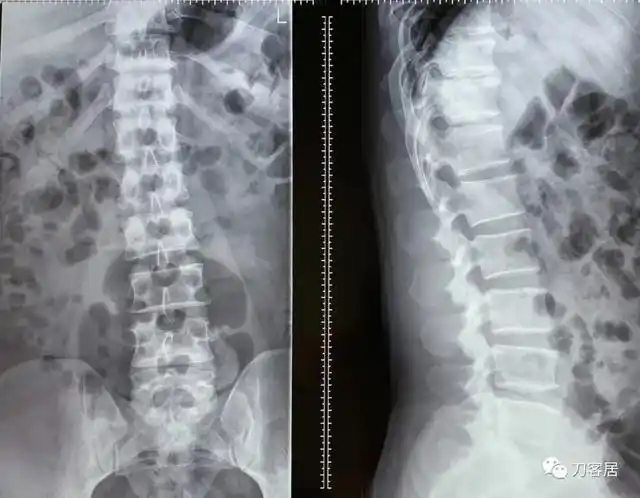

我的门诊病历:腰5骶1椎间盘突出症,保守治疗